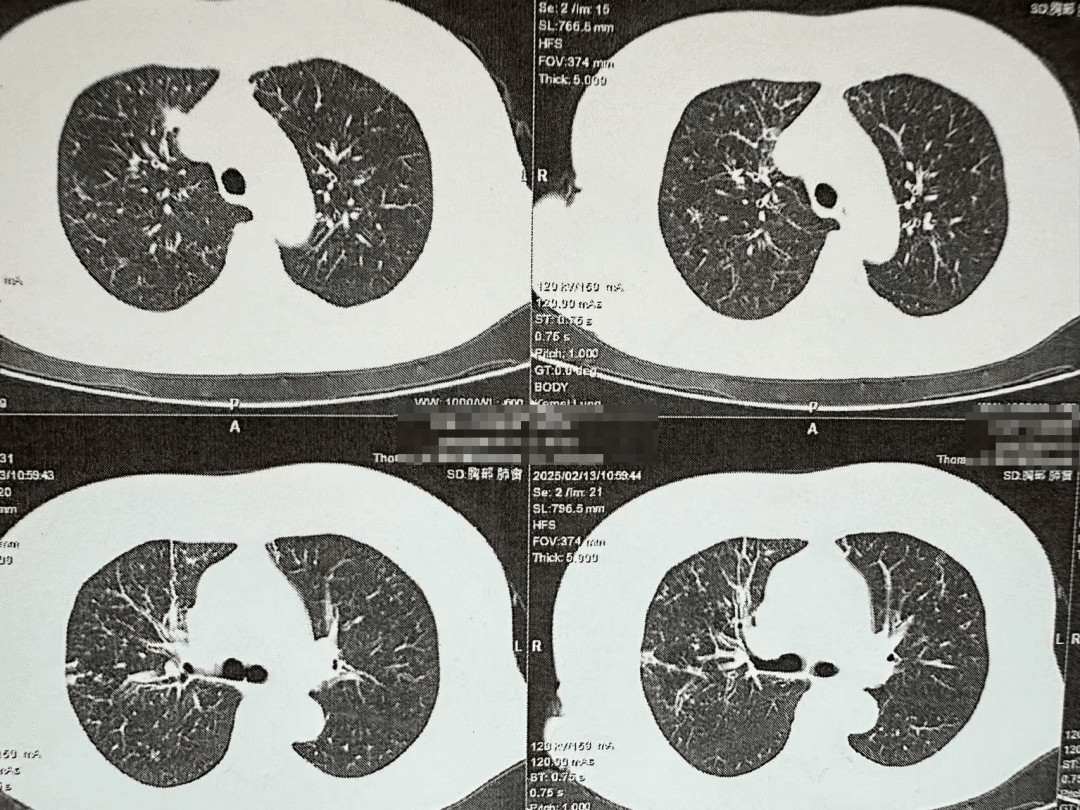

非HIV-PCP肺部影像

非HIV-PCP的早期症状与普通肺炎相似,但进展更快,48小时内可能引发呼吸衰竭。有免疫缺陷病史(如肿瘤化疗、器官移植、风湿免疫病长期用药)等高危人群一旦出现持续发热>1周,抗生素治疗无效;干咳、进行性呼吸困难;血氧饱和度<93%等症状应立即到呼吸与危重症医学科就医,进行支气管镜肺泡灌洗检查。